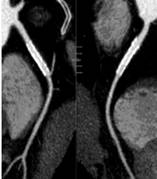

320排螺旋CT具备16cm宽覆盖探测器,实现动态容积扫描,360度的各向同性采集能力及[email protected]%密度分辨率的量子探测器,一次心跳全心脏采集,一圈扫描器官成像,一次检查完成多重任务,实现真正的动态容积体灌注及心脏、神经一站式检查;西门子Flash炫速CT扫描系统,具备两套同时旋转的X射线球管及探测器,实现了43cm/s的极快CT扫描速度和75 ms的时间分辨率,完成全胸扫描仅需0.6秒,使得患者做心脏扫描时无须食用β-受体阻滞药,亦无须屏气,并可实现低于1mSv的超低辐射剂量,配置第二代双能量、宽151级纯化能谱,组织鉴别能力进一步提高,可开展多达10余种双能量成像应用。

头颅一站式检查:320排容积CT覆盖范围达16cm,球管旋转一周可以覆盖整个脑组织,获得全脑0.5mm层厚各向同性全脑信息。一次扫描可以获得平扫容积图像、以时间为序列全脑动态3D-CTA图像(包括纯动、静脉期成像)及全脑灌注图像。一次检查即可排除脑出血、动脉瘤、动脉狭窄、梗塞、脑实质供血异常等多种病变及进行脑卒中筛查。